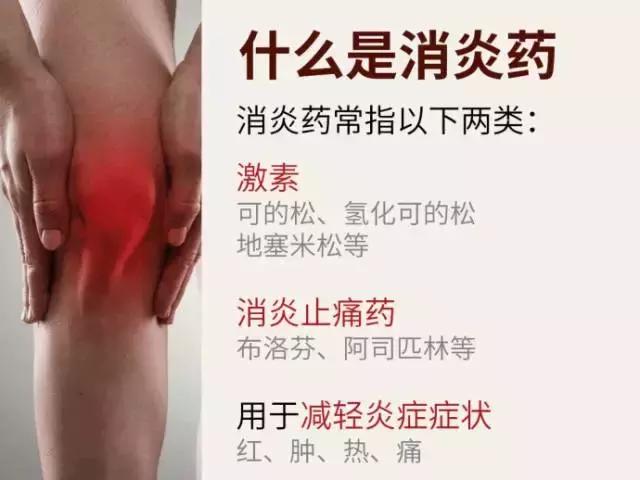

消炎药是用来减轻炎症的药物,在医学上叫解热镇痛药或者解热镇痛抗炎药;

「抗生素」和「消炎药」哪里不同?

简单来说,细菌感染可以引起炎症,但是炎症不一定都是由感染引起的,感染和非感染的因素都可以引起炎症。

所以说,这两种药并不对等,面对由病毒感染的炎症,抗生素无效。举个最普通的例子吧,人人都得过感冒,致病因素是病毒或者细菌,而抗生素只对细菌性感冒有用,它可以杀死致病细菌从而达到治疗的目的,但其实大部分感冒都是由于病毒引起的,选择多喝水可以自行痊愈或者感冒冲剂等药物也能抑制病毒达到治疗效果,那为什么要选择抗生素?